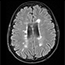

Esclerosis múltiple multifocal remitente-recurrente. A propósito de un caso